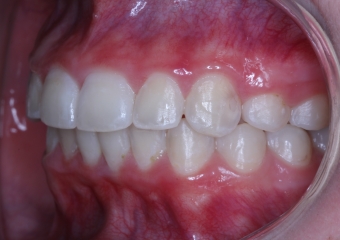

Lateral final - 2019